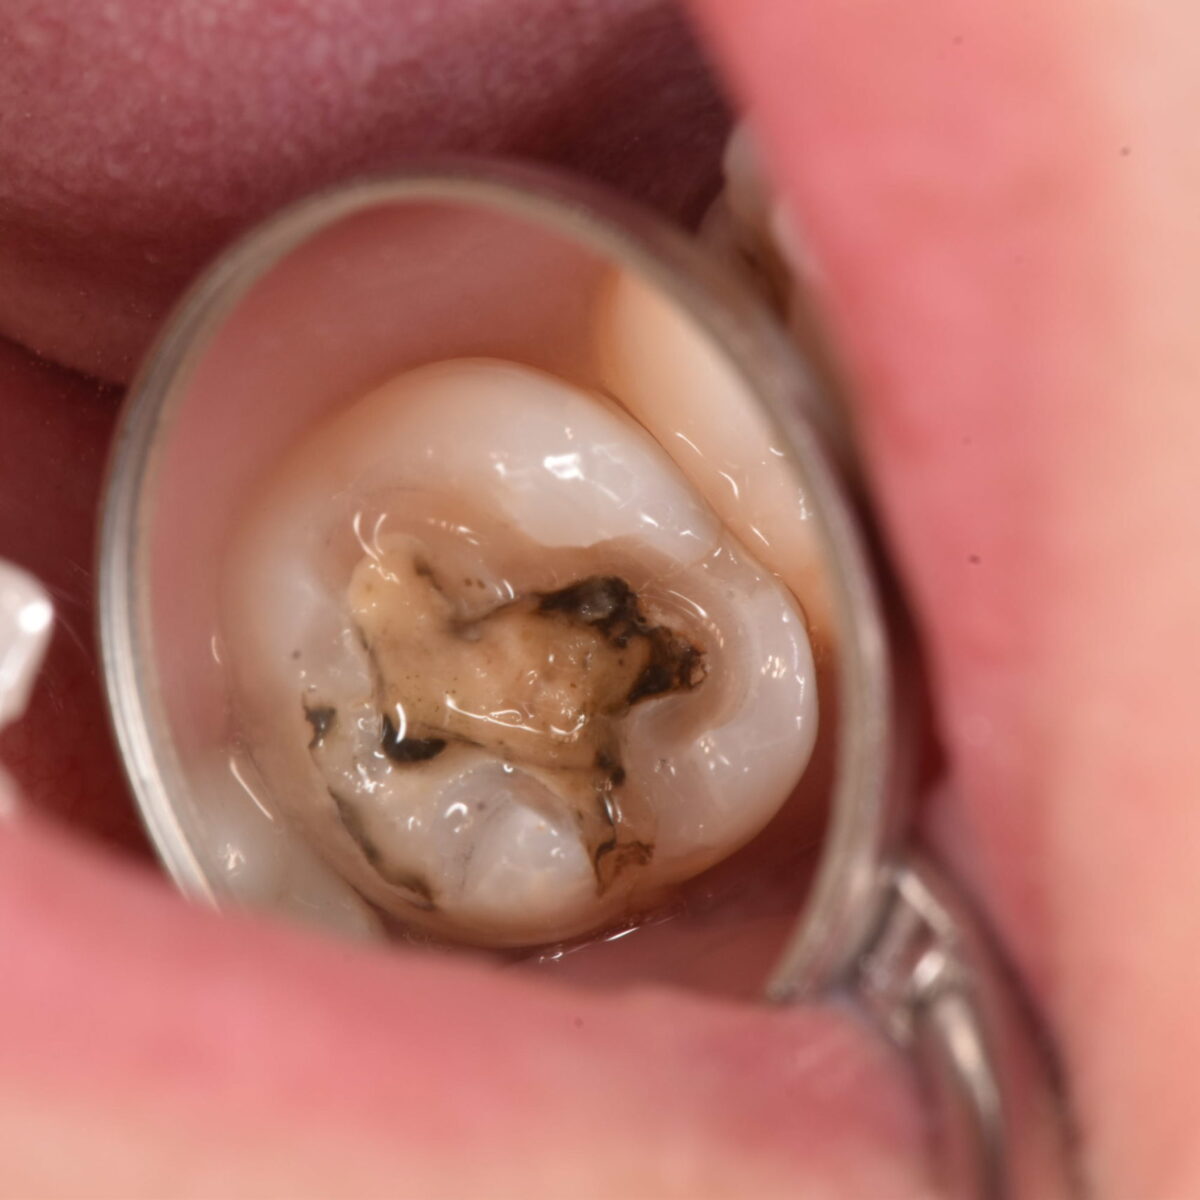

銀歯の下には・・・4

【東京メトロ東西線妙典駅 徒歩5分の歯医者】市川、妙典の歯科医院、めぐりデンタルクリニックの梶原です。 最近おさぼりですみません、がんばってまた書いていきますのでよろしくお願いしま…